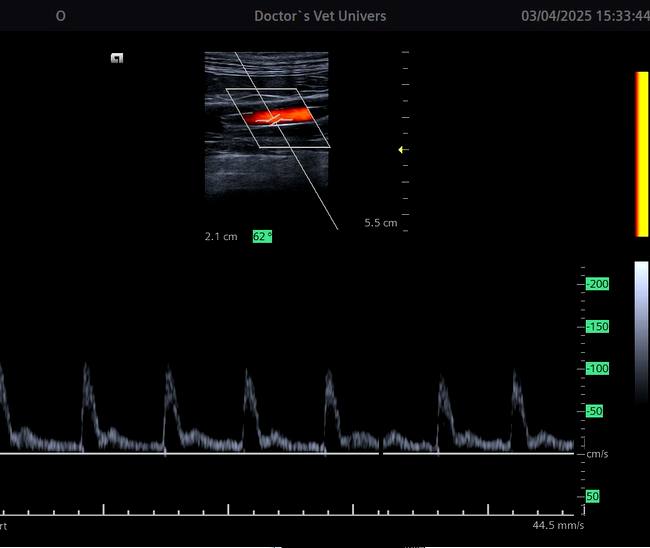

Angioplastia şi Stentarea în Boala Ocluzivă Ateromatoasă a Aortei Infrarenale (patologie extrem de rar întâlnită) la un câine de 16 ani realizată cu succes în premieră în România (şi rar efectuată la nivel internaţional) de către echipa AvantGarde CardioTeam în cadrul Laboratorului de Radiologie Intervenţională Veterinară “Doctor’s Vet Univers” Bucureşti, România.

Angioplasty and Stenting in Atheromatous Occlusive Disease of the Infrarenal Aorta (extremly rare diagnosed pathology) in a 16 years old dog successfully performed for the first time in Romania (and rarely effectuated internationally) by the AvantGarde CardioTeam in the Veterinry Interventional Radiology Laboratory “Doctor’s Vet Univers” Bucharest, Romania.